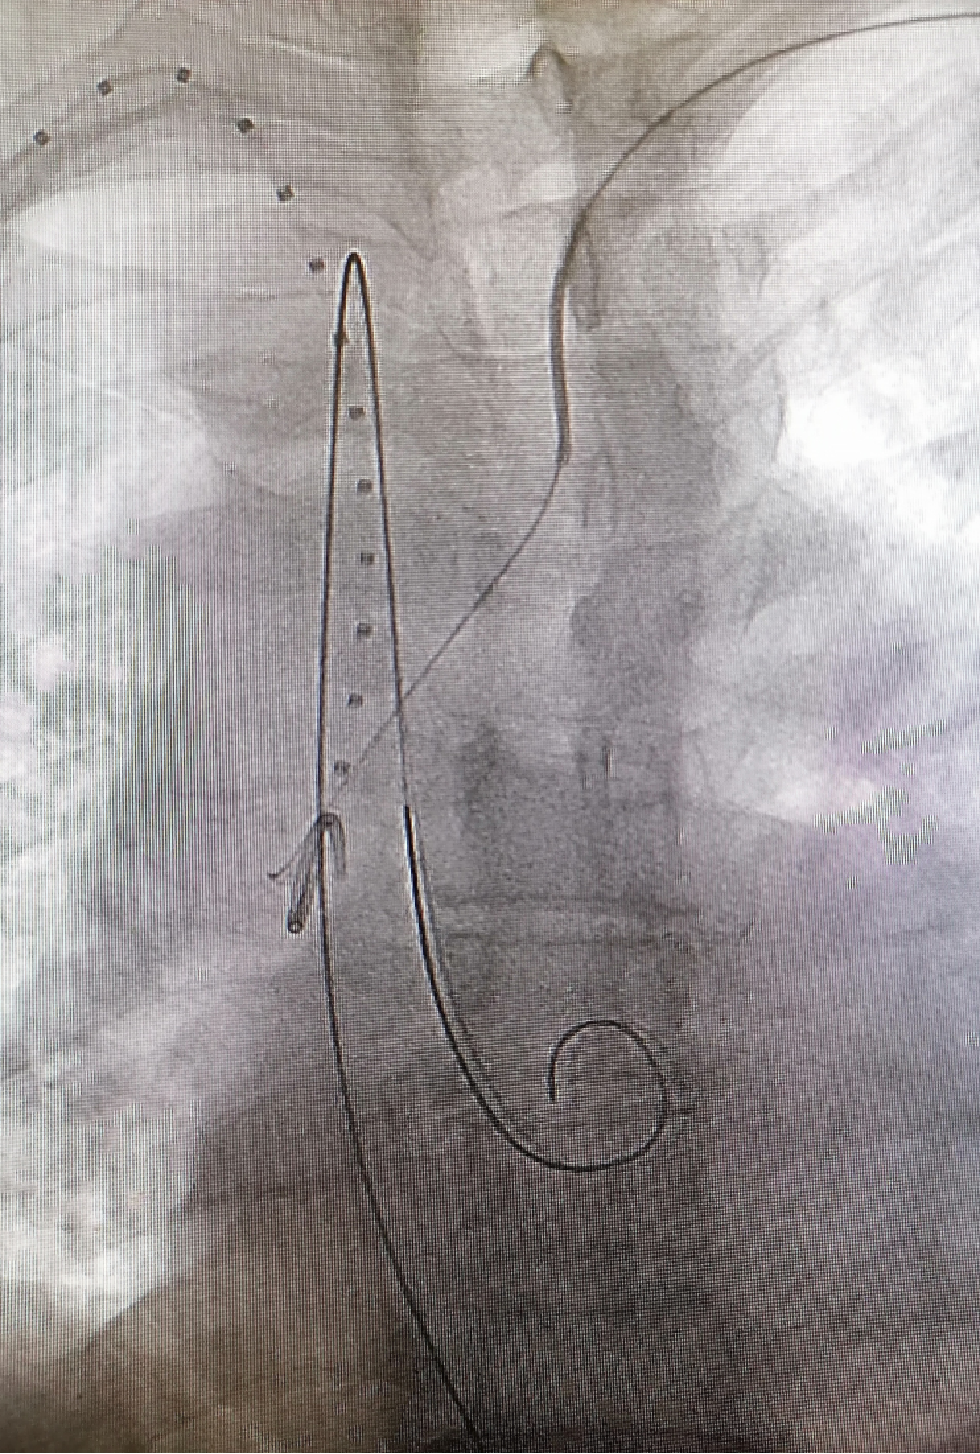

★Case 1 主动脉夹层+ALVA

治疗难点:弓上分支变异,夹层病变累及LSA,迷走左椎动脉

手术策略:

单分支

支架近端定位于LCCA

分支前缘预开窗(迷走左椎动脉)

结果:成功封堵破口,各分支通畅,左椎动脉保留